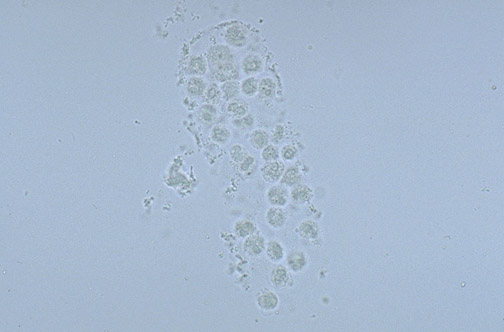

Here is a white blood cell cast that has formed in a distal renal tubule.